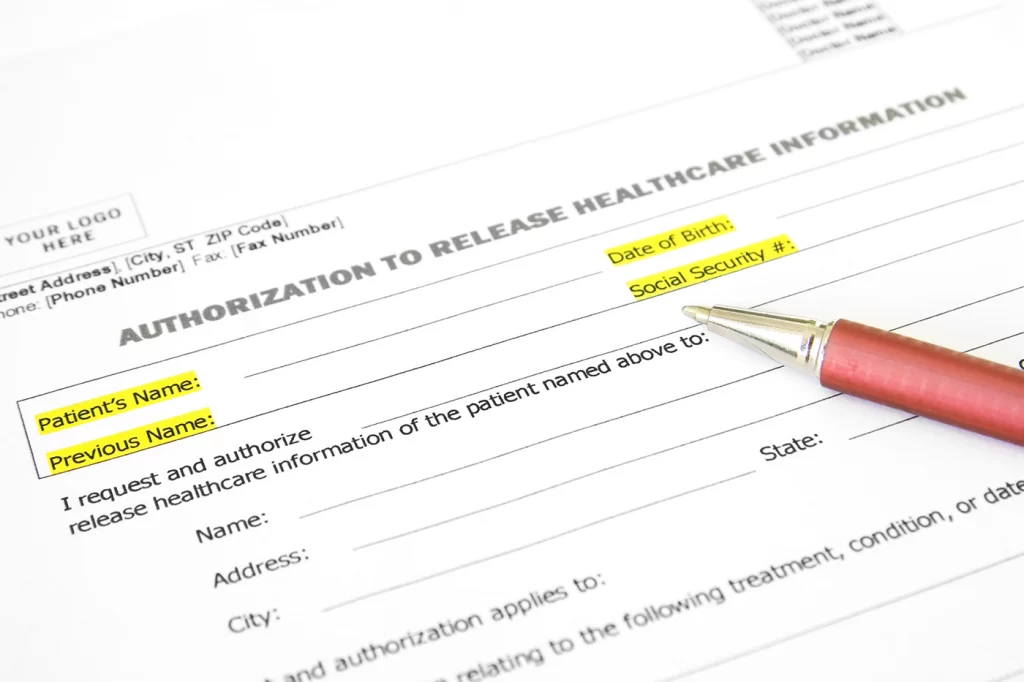

How many different logins and searches does it usually take for a single ROI request?

With LDA’s LegacyLinkTM – it’s just one.

With one click you can pull a single patient’s full archive across all retired systems on a single screen. No more trying to remember which application contains what data. We’ve done that work for you.